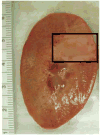

Our recent studies have shown that high-intensity pulsed ultrasound can achieve mechanical tissue fragmentation, a process we call histotripsy. Histotripsy has many medical applications where noninvasive tissue removal or significant tissue disruption is needed (e.g., cancer therapy). The primary aim of this study is to investigate tissue regions treated by histotripsy and to characterize the boundary between the treated and untreated zones using transmission electron microscopy (TEM). The nature of the tissue disruption suggests many clinical applications and provides insights on the physical mechanism of histotripsy. Fresh ex vivo porcine kidney tissues were treated using histotripsy. A 1 MHz 100 mm diameter focused transducer was used to deliver 15 cycle histotripsy pulses at a peak negative pressure of 17 MPa and a pulse repetition frequency (PRF) of 100 Hz. Each lesion was produced by a 3 × 3 (lateral) × 4 (axial) grid with 2 mm between adjacent lateral and 3 mm between axial exposure points using mechanical scanning. Two thousand pulses were applied to each exposure point to achieve tissue fragmentation. After treatment, the tissue was processed and examined using TEM. Extensive fragmentation of the tissues treated with histotripsy was achieved. TEM micrographs of the tissue treated by histotripsy, showing no recognizable cellular features and little recognizable subcellular structures, demonstrates the efficacy of this technique in ablating the targeted tissue regions. A boundary, or transition zone, of a few microns separated the affected and unaffected areas, demonstrating the precision of histotripsy tissue targeting. TEM micrographs of the tissue treated by histotripsy showed no discernable cellular structure within the treated region. Histotripsy can minimize fragmentation of the adjoining nontargeted tissues because, as a nonlinear threshold phenomenon, damage can be highly localized. The potential for high lesion precision is evident in the TEM micrographs.